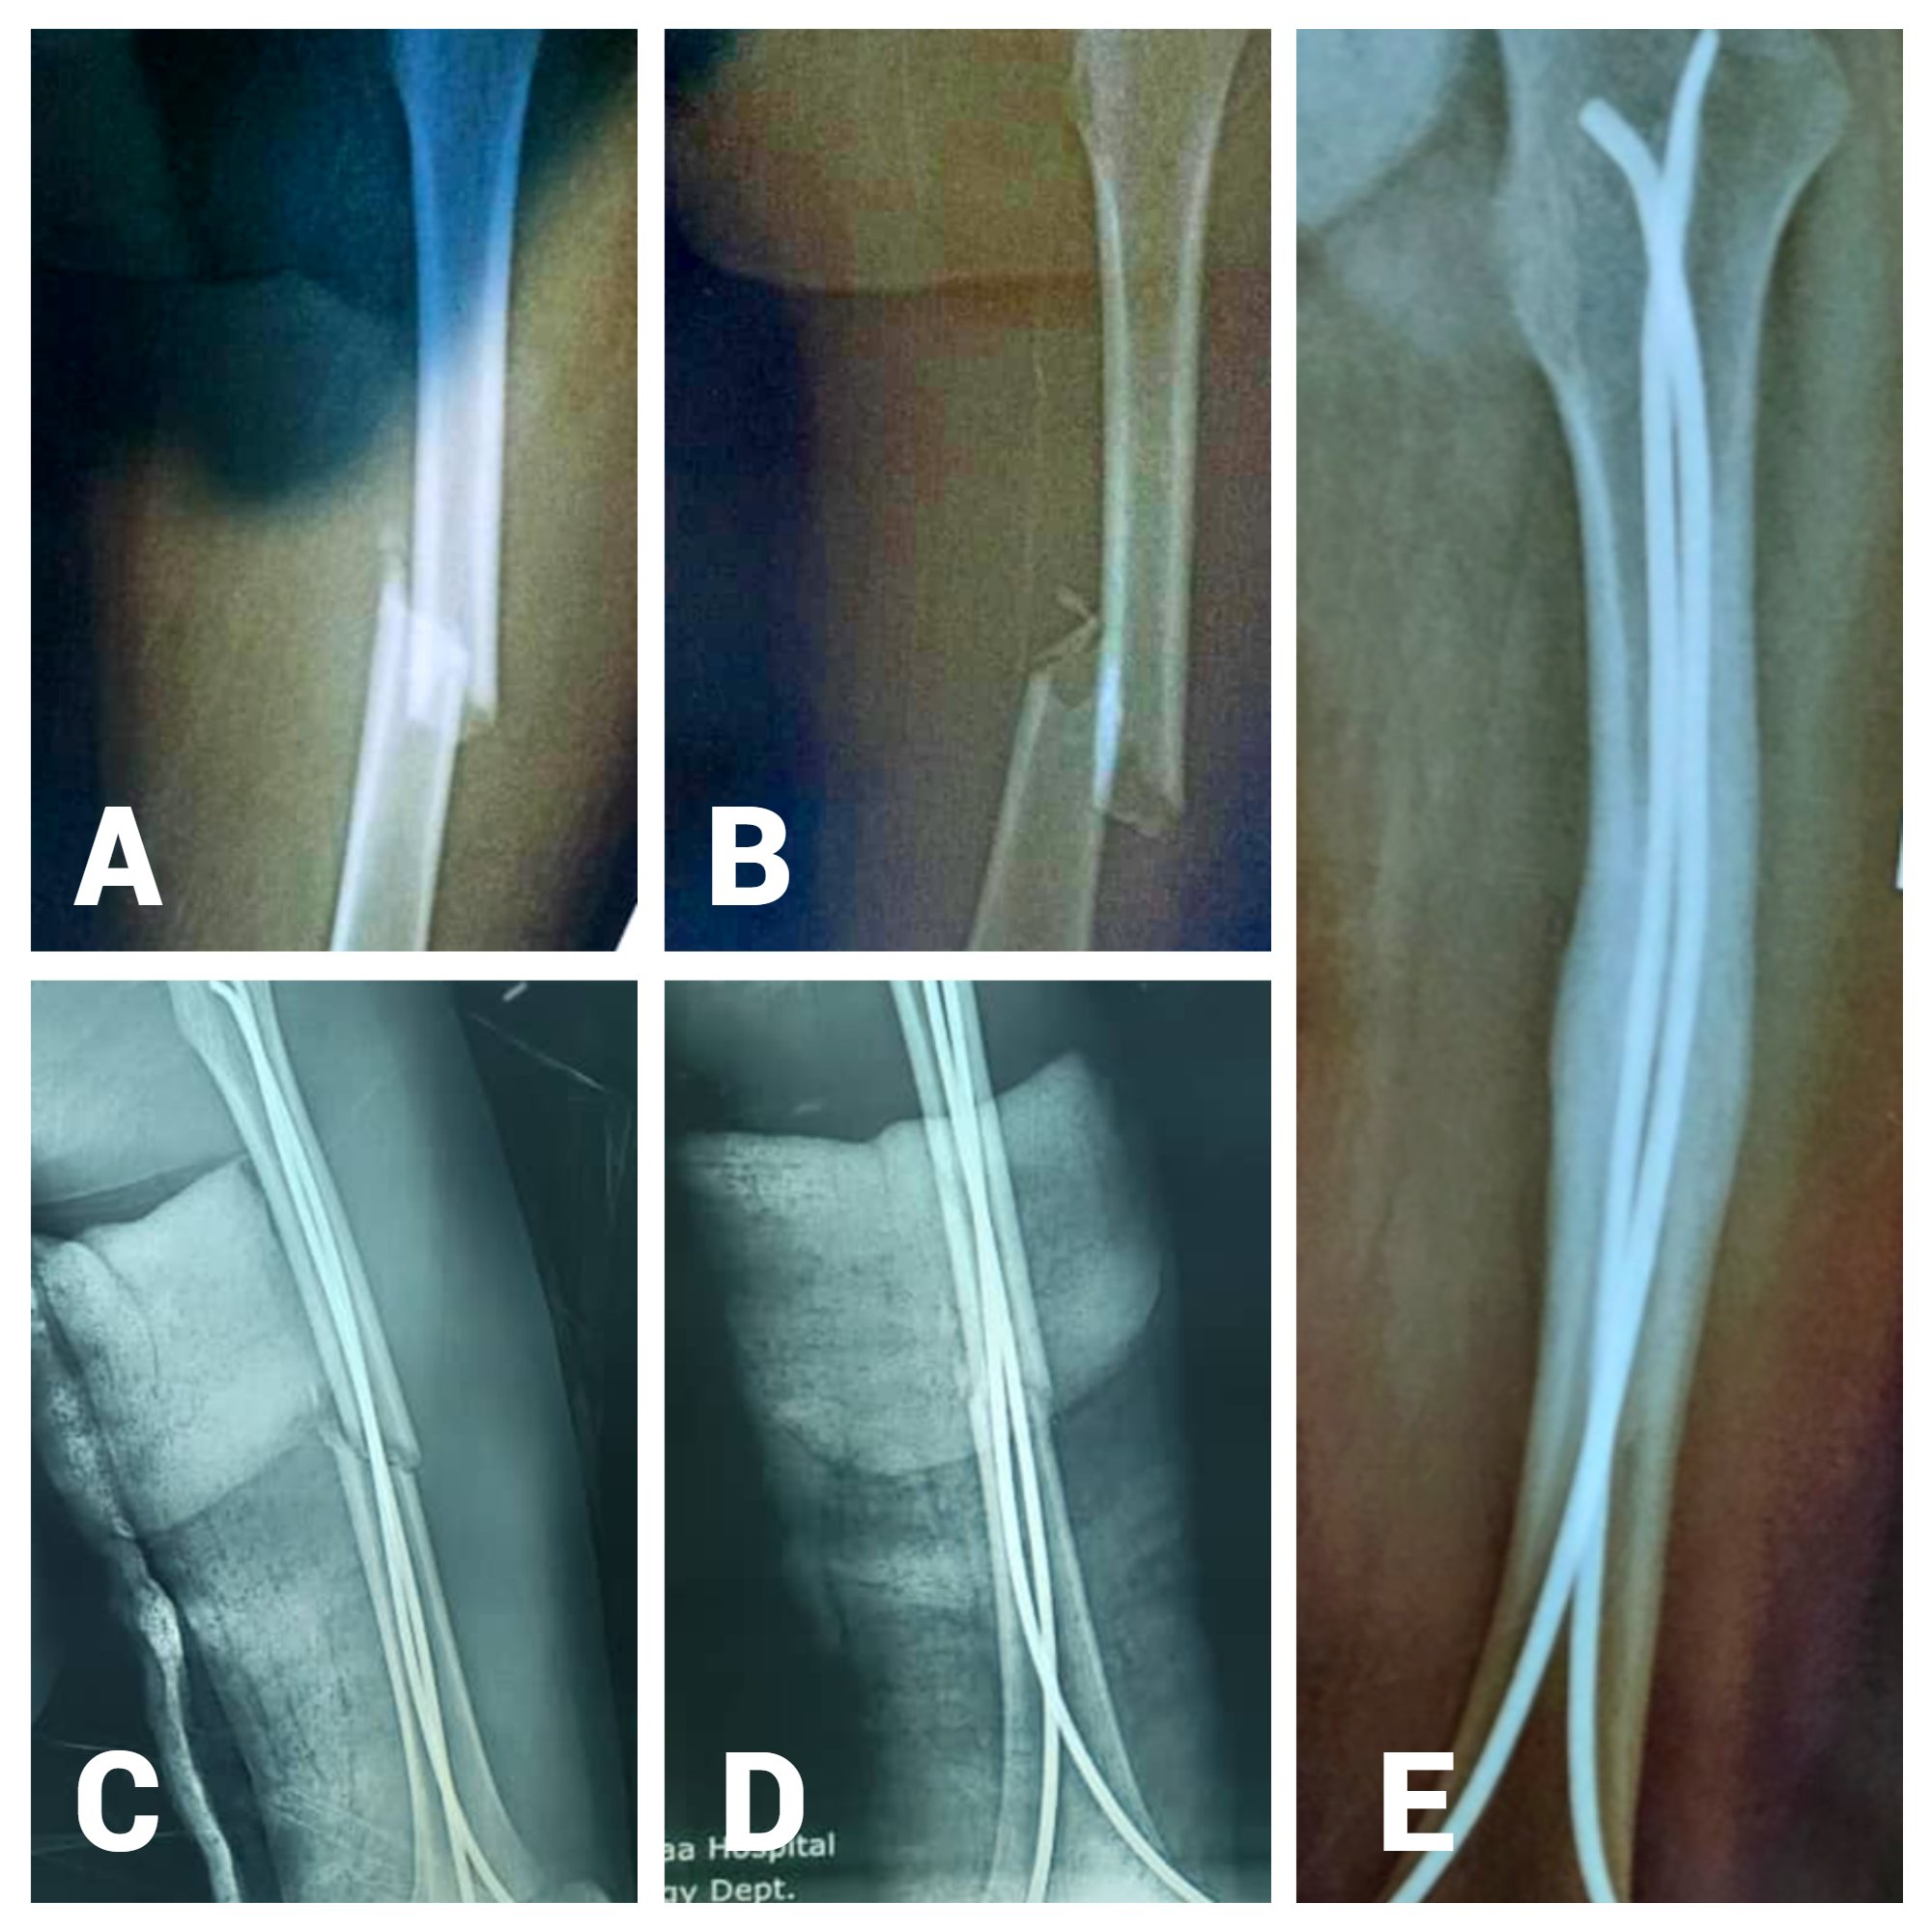

Introduction: This study aimed to evaluate the functional outcomes of pediatric femoral shaft fractures treated with a Titanium Elastic Nailing System (TENS) in two tertiary hospitals in Sana'a, Yemen, between 2021 and 2023. The primary objective of this study was to assess the efficacy and safety of TENS for achieving bone union, restoring limb function, and minimizing complications in a resource-limited setting.

Materials and methods: This prospective observational study was conducted at Al-Thawra Modern General Hospital and Al-Kuwait University Hospital, Sana'a, Yemen. Twenty children aged six–13 years with closed unilateral femoral shaft fractures were treated using TENS. Functional outcomes were assessed using Flynn's criteria, which evaluates alignment, leg length discrepancy, and perioperative complications. Follow-up visits were conducted four, eight, 12, and six months postoperatively.

Results: The mean age of the participants was 9.06 ± 1.9 years, with 14 males (70%) and six females (30%). Road traffic accidents were the most common cause of injury (10 cases, 50%). Excellent functional outcomes were observed in 15 cases (75%), and satisfactory outcomes in five cases (25%). Complications were minimal, with pain at the nail insertion site reported in three patients (15%), limb length discrepancy in one patient (5%), and malalignment in one patient (5%). No major complications such as nonunion or infection were observed.